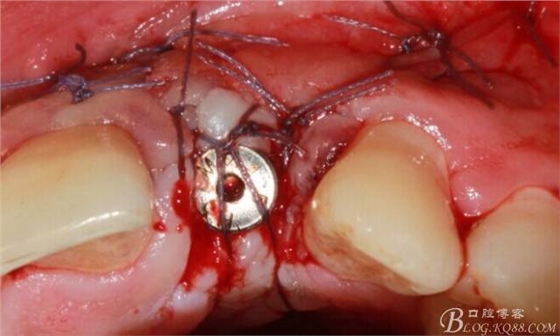

縫合。

術(shù)后X光片。